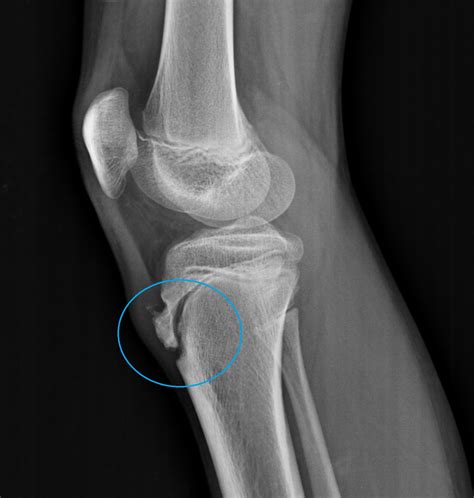

Diagnosing Osgood-Schlatter disease typically involves a physical examination and a review of the patient's medical history. The healthcare provider will ask about the symptoms, the onset of pain, and any recent changes in physical activity. They will also perform a physical examination to assess the affected knee, checking for tenderness, swelling, and any visible bumps.

In some cases, imaging tests such as X-rays, ultrasound, or MRI may be ordered to rule out other conditions and confirm the diagnosis. These tests can help visualize the tibial tuberosity and the patellar tendon, providing a clearer picture of the inflammation and any underlying issues.